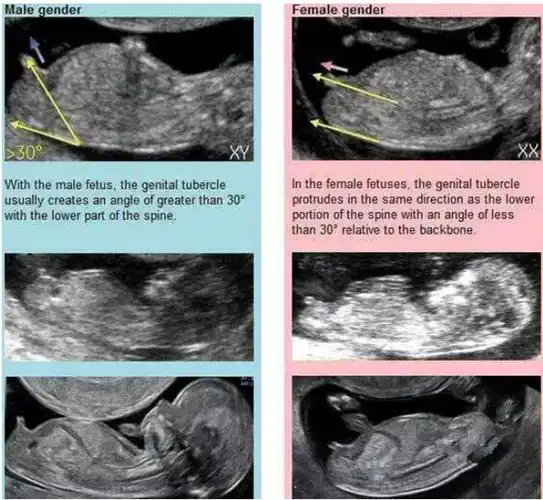

b超三条白线是女孩nt三个亮点是男孩女孩